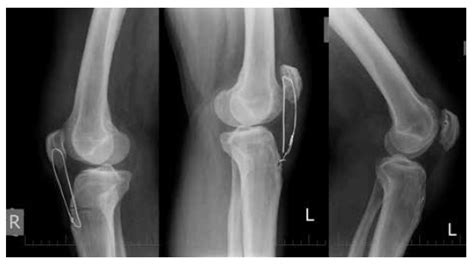

Dôležitosť RTG Vyšetrenia a Návštevy Pohotovosti

Niektorí rodičia sa rozhodnú čakať doma, kým sa predmet nevylúči, ak dieťa nevykazuje žiadne známky problémov. Avšak, ako zdôrazňuje viacero príspevkov, návšteva pohotovosti a RTG vyšetrenie môže poskytnúť cenné informácie. RTG snímka ukáže presnú polohu mince alebo predmetu v tráviacom trakte. Lekári na pohotovosti vedia odhadnúť riziko a odporučiť ďalší postup. Jeden z rodičov uviedol, že ich dieťa malo 5-centovku a sťažovalo sa na bolesť chrbta. Po RTG snímke lekári zistili, že minca je už v dolnej časti tráviaceho traktu a odporučili čakať. Iný rodič opisuje skúsenosť, kedy dieťa prehltlo 20-centovku a po návšteve pohotovosti im bolo odporučené dať mu veľa vláknitej stravy, pričom kontrolný RTG potvrdil, že minca sa nepohla.